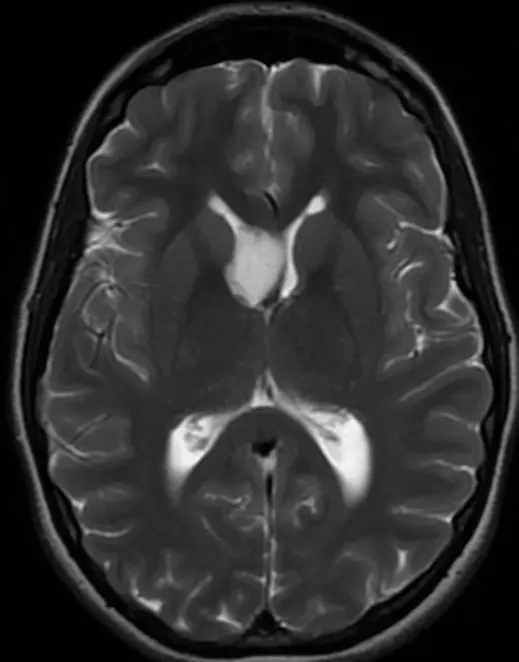

肿瘤在MRI影像中有什么表现?

在MRI影像中,黏液样胶质神经元肿瘤通常表现为T1加权图像上的低信号、T2加权图像上的高信号,并且在T1对比增强图像中无增强表现。这些肿瘤通常边界清晰、呈分叶状。

影像学检查中有什么样的特点?

这些肿瘤在影像学上表现为边界清晰的分叶状肿块,通常在T2-FLAIR图像中呈现外围高信号和中心低信号,并且无周围水肿。